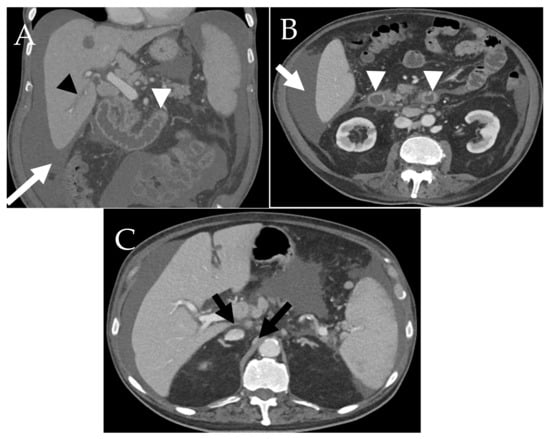

6.2. GI Tract, Liver and Spleen

6.2.1. GI Tract

6.2.2. Liver and Spleen

- Avila, N.A.; Ling, A.; Worobec, A.S.; Mican, J.A.M.; Metcalfe, D.D. Systemic mastocytosis: CT and US features of abdominal manifestations. Radiology 1997, 202, 367–372. [Google Scholar] [CrossRef] [PubMed]